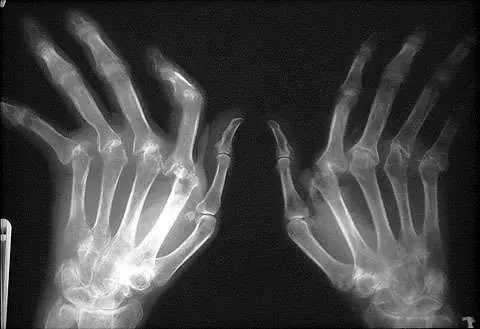

Cambios radiológicos compatibles con AR.